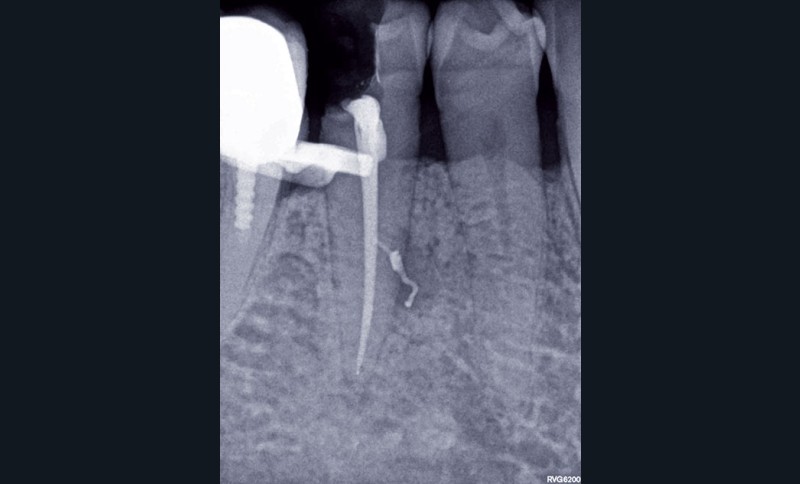

1. Une radiographie rétro-alvéolaire centrée sur 45 met en évidence une reprise de carie sous la restauration en composite et une lésion inflammatoire périradiculaire d’origine endodontique (LIPOE). Le test de vitalité est négatif.